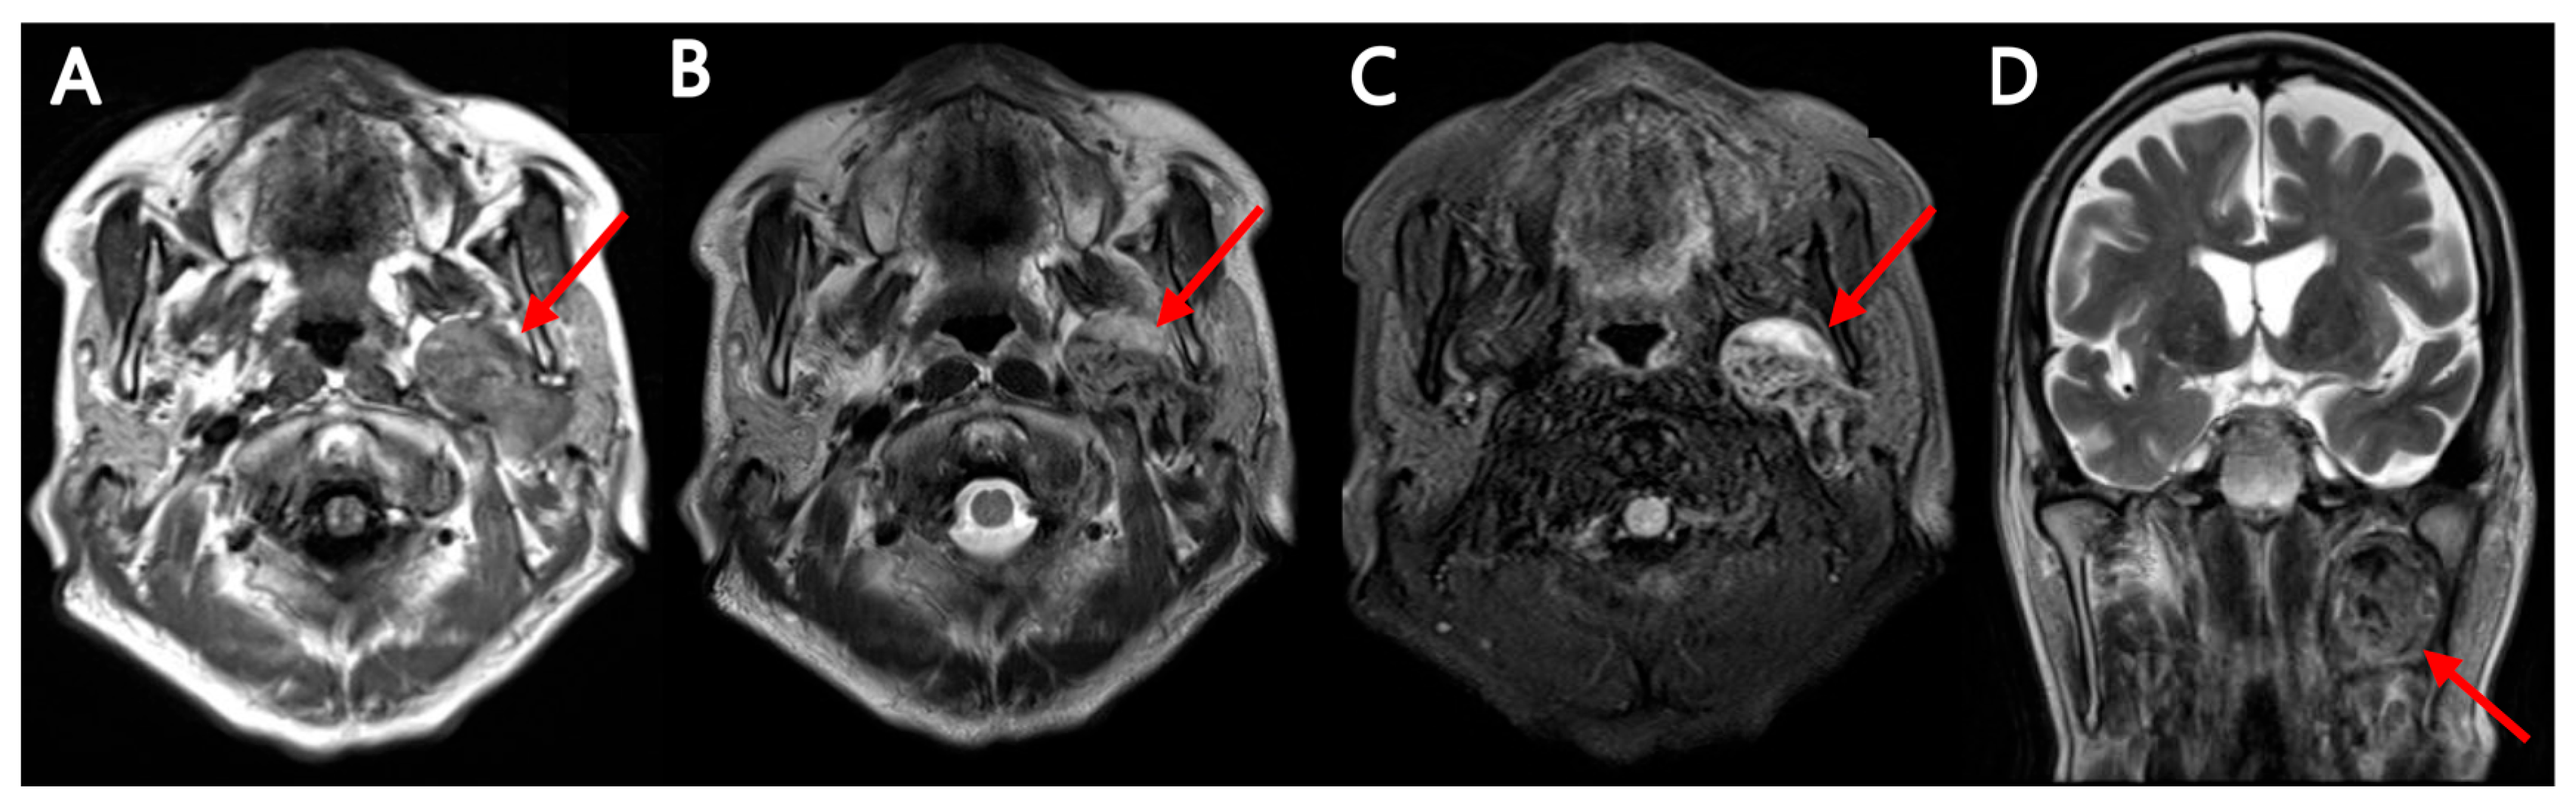

Multimodality Imaging of Warthin’s Tumor: PET/CT, Scintigraphy, MRI, and CT